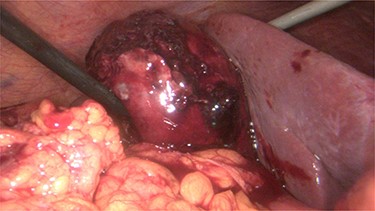

A 68-year-old male with arterial hypertension, dyslipidemia, cerebrovascular disease and a history of coronary heart disease, who had already done several percutaneous coronary interventions with stent placement, went to the emergency department with precordial pain and vomiting. At admission, he had an electrocardiogram in sinus rhythm with negative T waves V4–V6, DI and aVL. His blood test revealed leukocytosis 13 790/l with neutrophilia 11 600/l and polymerase chain reaction (PCR) 0.05 mg/dl, with normal cardiac markers. The pain improved with sublingual nitroglycerin. He was admitted and, on the next day, underwent a coronary angiography with angioplasty on the second diagonal of the anterior descending artery with stent placement due to a 70–90% lesion. During the procedure, he performed 5000 Units of heparin and 1 mg of isosorbide dinitrate. After the procedure, he was obnubilated and hypotensive, which improved with fluid challenge. New blood test was taken with evidence of increased leukocytosis to 17.540/l, PCR to 16.4 mg/dl, total bilirubin to 1.52 mg/dl, direct bilirubin 0.74 mg/dl, with normal aminotransferases and gamma-glutamyl transferase. Blood cultures, urine culture, chest X-rays were performed, and empiric antibiotics were started with piperacillin/tazobactam, and the consultation of general surgery was requested. In the evaluation it stands out that the patient was hypocoagulated and with dual antiplatelet therapy, with abdominal pain and defense in the upper quadrants. In blood test he had a slight increase in the international normalized ratio (INR) of 1.26 and in the prothrombin time. An abdominal ultrasound and CT scan (Fig. 1) was performed with evidence of gallbladder hydrops, with high-density contents suspected of thick mud, or hematic content, with a thickened gallbladder wall (~ 4–5 mm), with perivesicular fluid and perivesicular fat densification favoring the hypothesis of acute cholecystitis (Fig. 1). In this context, the patient underwent laparoscopic cholecystectomy on the same day with intraoperative diagnosis of acute gangrenous cholecystitis with intravesicular hematoma and hemoperitoneum (~450 cc) (Fig. 2 and video 1).

Abdominal CT scan showing the gallbladder with high-density contents.

In the postoperative period, the patient evolved well, ending up being discharged on the ninth day of hospitalization. The gallbladder histology showed intense congestion and extensive hemorrhagic areas compatible with lesions of acute purulent hemorrhagic cholecystitis.